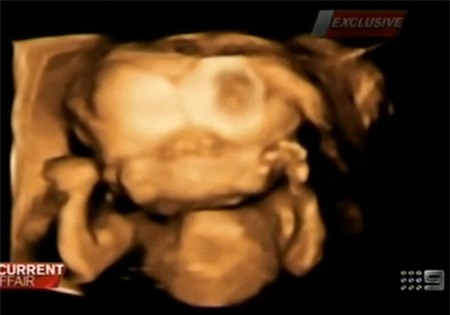

Hình ảnh siêu âm 3D cho thấy đứa bé chỉ có một thân người nhưng lại có đến 2 khuôn mặt |

Các bác sĩ đã nói với Renee Young và Simon Howie rằng, đứa trẻ không thể sống sót quá 2 ngày sau khi sinh, mà kể cả nếu có cố chữa trị, chi phí cũng sẽ rất đắt. Tuy nhiên, cặp đôi vẫn từ chối việc bỏ thai nhi, mặc dù họ đã có 7 đứa trẻ trước đó.